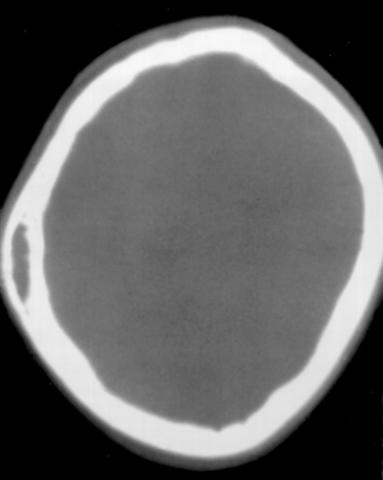

Рис. 7. Аксиальная компьютерная томограмма (в костном режиме) при гемангиоме левой теменной кости: имеется линзовидный участок пониженной плотности, соответствующий локализации гемангиомы в губчатом слое кости, наружная и внутренняя костные пластинки не изменены.